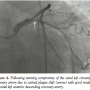

The current coronary angiogram revealed again a significant in-stent restenosis at this site as well as a significant de novo ostial LAD stenosis involving part of the distal LM stem (Figure 1). The left circumflex (LCX) coronary artery, including the ostial segment, was free of significant disease. The mid and distal LAD stents were widely patent and the left ventricular systolic function was normal.